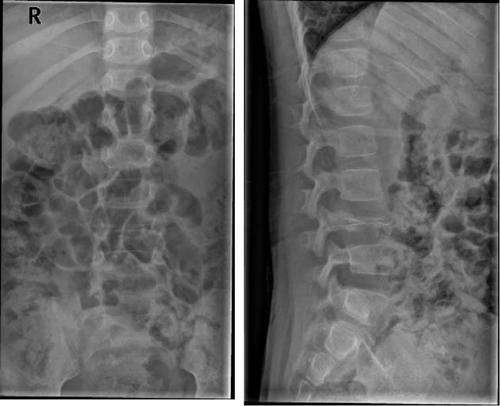

Giant cell tumor of bone 骨巨细胞瘤

好发于20~40y,起于椎体,向附件发展

单纯溶骨性骨质破坏,有偏心性,膨胀明显;椎体变扁时肿瘤呈前后哑铃状膨胀(较有特征)

有骨包壳形成,可伴骨皮质中断,无周围硬化及基质钙化。

在骶骨者,好发于上部骶椎(脊索瘤:S3-5)

Case15:F,41y;下腰部疼痛7年余,加重1周。